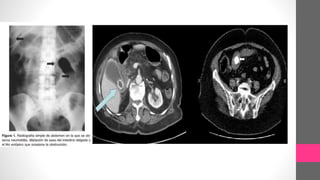

Radiografia Abdominal:

Triada de Rigler. Neumobilia,

imagen radiopaca ectopica

(lito) y distensión intestinal +

cambio de posición del lito

en relación al estudio

radiográfico previo.

DIAGNÓSTICO Triada de Mordor: • Historiade litiasis vesicular • Signos clinicos de colecistitis • Obstruccion intestinal Radiografia Abdominal: Triada de Rigler. Neumobilia, imagen radiopaca ectopica (lito) y distensión intestinal + cambio de posición del lito en relación al estudio radiográfico previo.  Ultrasonido  Tomografía contrastada

• #22 Fig. 4: Gran litiasis biliar (marcada con flecha) en paciente asintomática. Corte axial de la TAC que muestra la presencia de un cálculo impactado en el intestino